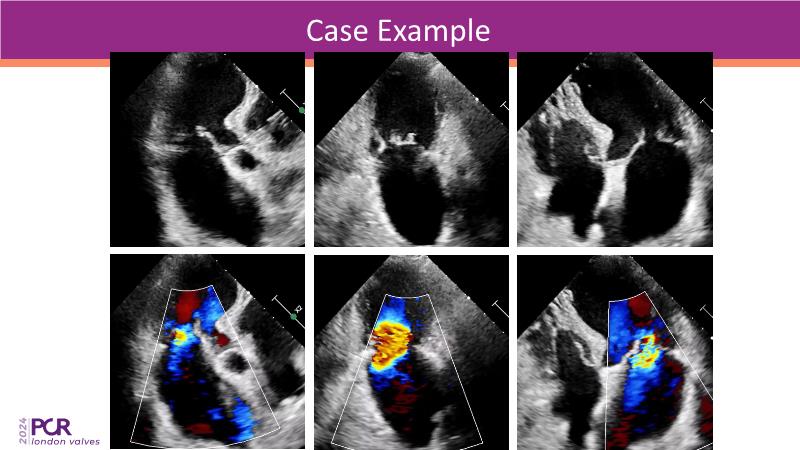

Cinch it if you can - Indirect annuloplasty for functional mitral regurgitation

This session on mitral regurgitation offers an in-depth look at the EMPOWER trial outcomes, indirect annuloplasty in aFMR, and remodeling with the CARILLON device. Explore the benefits of early treatment for secondary mitral regurgitation, understand the role of left ventricular reverse remodeling, and review the latest clinical evidence supporting indirect annuloplasty. Discover how this technique keeps future treatment options open while expanding therapeutic possibilities for aFMR.